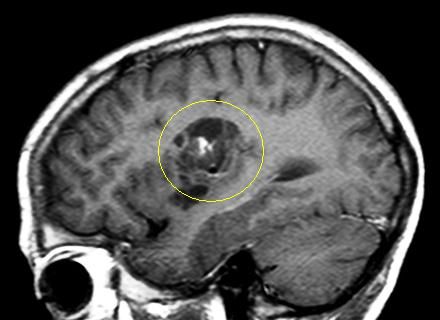

Es handelt sich um ein bildgebendes Verfahren, bei dem die Patienten in einer Röhre liegen und währenddessen mit Hilfe von wechselnden Magnetfeldern nach einem speziellen Epilepsie-Protokoll Bilder des Gehirns gemacht werden. So können Tumoren, Fehlbildungen oder andere Veränderungen des Gehirns, die Anfälle verursachen können, sichtbar gemacht werden. Durch moderne computergesteuerte Nachbearbeitungsmethoden oder Überlagerung mit anderen Bildmodalitäten können Läsionen dann noch besser dargestellt werden.

• Eine Gehirnläsion, die chirurgisch entfernt werden kann. Besonders wenn die Anfälle von einer umschriebenen Läsion (z.B. Tumor, Vernarbung, Fehlbildung) ausgehen, die chirurgisch gut entfernt werden kann, besteht eine hohe Chance auf Anfallsfreiheit.

Folgende Veränderungen oder Erkrankungen des Gehirns werden häufig und mit gutem Erfolg (70-80% Anfallsfreiheit) epilepsiechirurgisch behandelt:

Tumoren